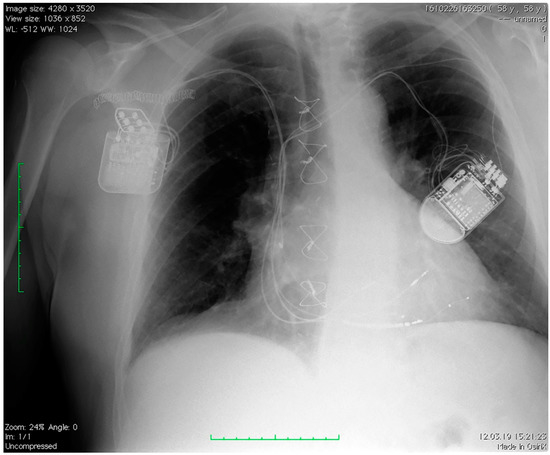

| CRT/ICD device | MAXIMO IIVRD284VRC, MEDTRONIC | MAXIMO II DR, MEDTRONIC | LUMAX 340 HF-T, BIOTRONIK | IFORIA 3 HF-T, BIOTRONIK | IFORIA 3 DR-T, BIOTRONIK |